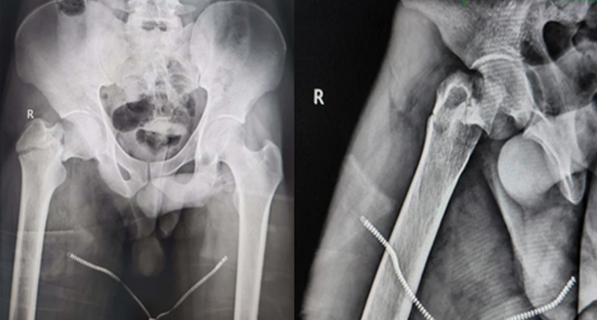

A 23-year-old male was admitted to our emergency department 2 h following a road traffic accident, sustaining injury to the right hip. On presentation, patient had pain in the right hip with inability to bear weight on the same side. Radiographs revealed the presence of neck of femur fracture accompanied with a fracture of the GT (Fig. 1).

Figure 1: Pre-operative anteroposterior and lateral radiographs